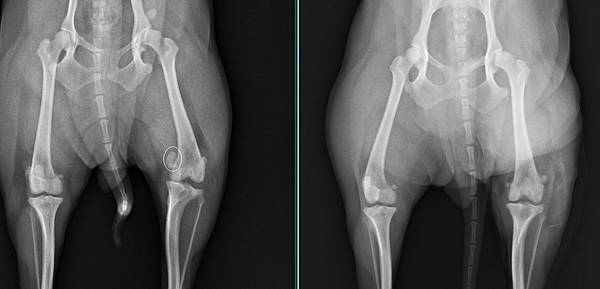

檢查發現是膝蓋骨異位

於是安排手術改善膝蓋骨的狀況

手術後啾啾也很快恢復走跳的能力